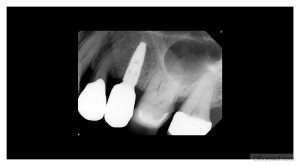

Implant Radiology | Myths vs. Facts

Learn how to maximize the diagnostic value of Cone Beam Computed Tomography (CBCT) while minimizing radiation exposure for safer imaging and smarter decision-making in dentistry.